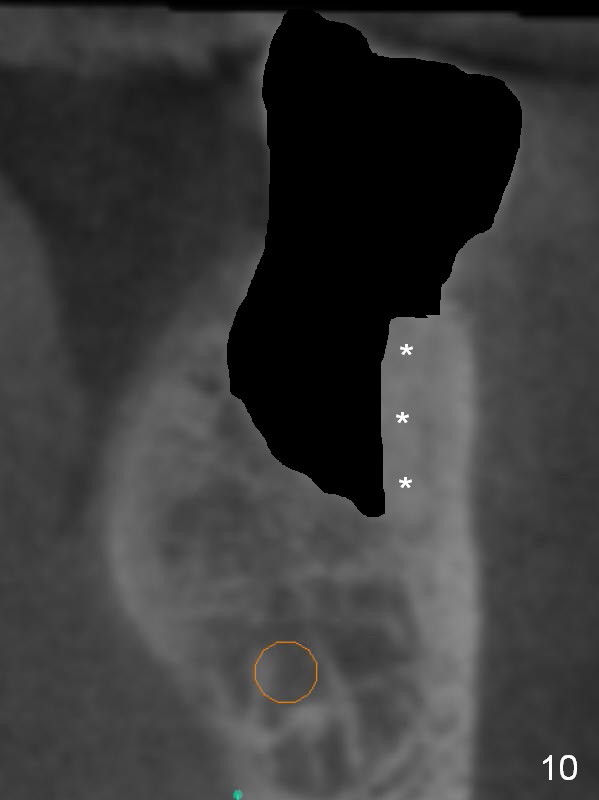

Coronal section through the distal root (Fig.8 D) shows that the lingual plate (Fig.9 (post extraction (Metronidazole)) L) looks thicker than the buccal one (B). When socket shield is performed in the distal root (Fig.10 *, surgical bur block with long surgical fissure bur), there will be less chance to place pressure on the thin buccal plate. The 6.9x10 mm implant may be oversized (Fig.11). Prepare DIO Sinus Master Kit so that 3-4 mm stoppers can be used for osteotomy.